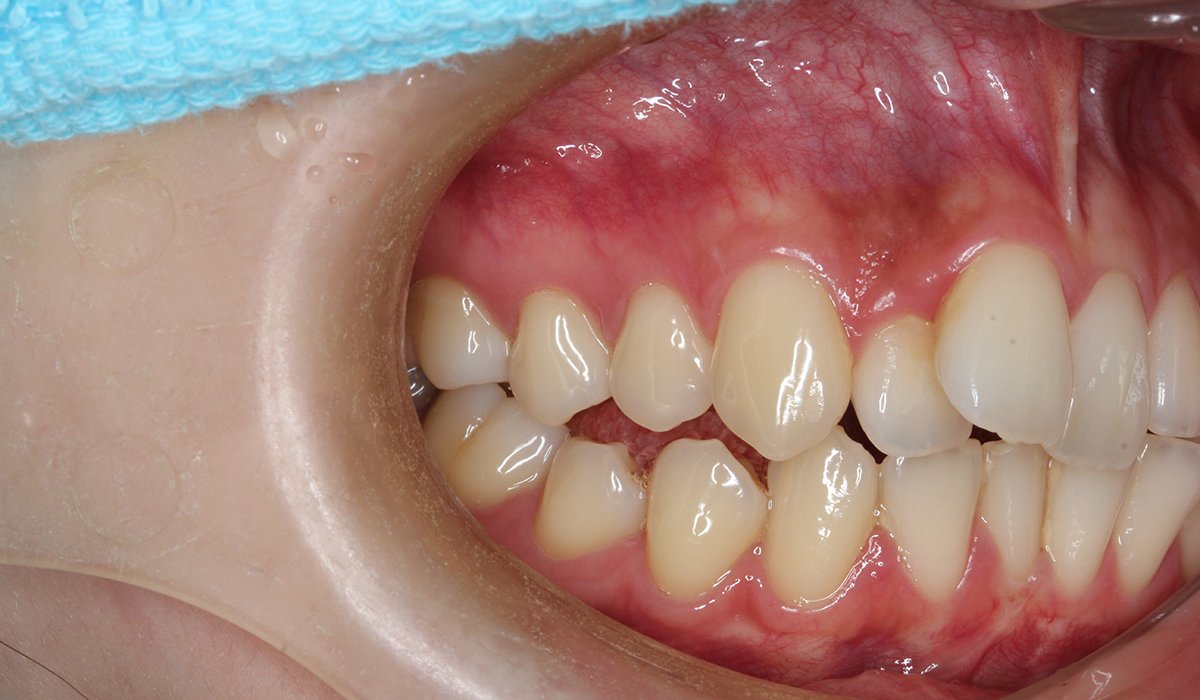

今回ご紹介する患者様は、全体的な歯のガタツキを気にされており、矯正検査後叢生Ⅰ級と診断いたしました。

右側

術前

BK終了時

術後